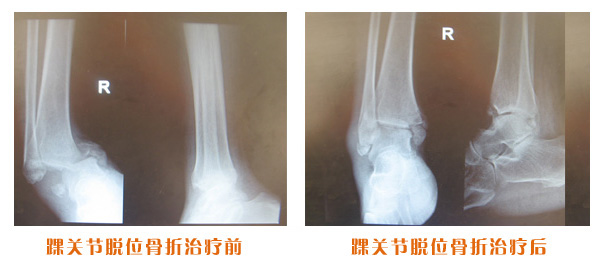

肥城市安駕莊梁氏骨科醫院是一所以梁氏手法正骨配合膏藥為特色的現代化專科醫院。

梁氏骨科術始創于清雍正年間,歷經八代,至今已有三百年歷史。據1929年泰安縣志載“梁瑞圖先生,字增生,號蓮峰,安駕莊人,精岐黃并發(fā)明接骨,凡跌打車凡跌打車軋皮不破而碎骨者......【詳細】 |